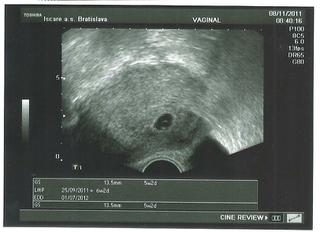

@lauritka no, hádam až tak veľmi nie...🙂. TOto meranie je len odhadom, nikdy nie je presné. Ale okolo tých 3 kg by som brala...🙂